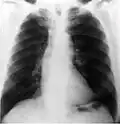

Radiografía

En este segmento de las imágenes médicas se puede encontrar desde los más simples exámenes de rayos X hasta estudios complejos como el sistema digestivo. Las imágenes son obtenidas gracias a las diferentes capacidades que poseen los tejidos de atenuar las radiaciones X, han sido utilizados en el ámbito médico desde su descubrimiento en 1895 por Wilhelm Conrad Röntgen y hasta nuestros días son ampliamente utilizados para realizar diagnósticos diferenciales en el área de la traumatología (pesquisa de fracturas, alteraciones de los huesos y malformaciones), a la vez permiten visualizar algunos órganos de menor densidad como los pulmones, en cuyo caso es posible detectar diferentes patologías que afectan a este órgano cono es el caso de la acumulación de polvos que al ser inhalados causan enfermedades definidas como silicosis. Todo estudio radiográfico está compuesto, a lo menos, por dos proyecciones lo que permite visualizar la estructura estudiada en dos planos perpendiculares.

Este método de adquisición de imágenes puede ser asociado con el uso de medios de contrastes, hidrosolubles sobre la base de bario o yodo dependiendo de la vía de administración, los que permiten realizar estudios específicos del sistema digestivo, urinario lo cual facilita el diagnóstico de una gran variedad de patologías. Desde su descubrimiento hasta la actualidad son muchas las transformaciones que han afectado a los equipos utilizados para tomar radiografías, todas ellas tendientes a reducir de manera considerable la exposición a radiaciones ionizantes tanto de los profesionales (médicos y tecnólogos médicos) que obtienen las imágenes, como la irradiación a la cual está expuesto el paciente. En los últimos años, con la llegada de los equipos digitales, las dosis de radiación utilizadas para obtener un mismo examen se han reducido de manera considerable (la primera radiografía de una mano que se obtuvo demoró casi 15 minutos de exposición, hoy el mismo examen puede ser adquirido con apenas 20 a 30 milisegundos de exposición) lo que puede implicar una reducción de dosis considerable que podría llegar a ser más de 1000 veces menor.